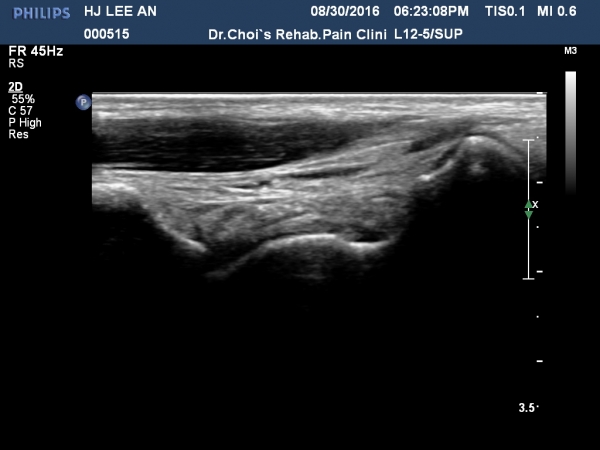

¹ß¸ñ ¾ÕÂÊ Á¾´Ü¸é°Ë»ç¿¡¼­ °üÀý³» ¼ö¾×Àú·ù´Â ¶Ñ·ÈÇÏÁö ¾ÊÀ¸³ª °æ°ñ °Å°ñ Á¢Ã˺ο¡ ¼Ò·®ÀÇ

¼ö¾×Àú·ù°¡ °üÂûµÊ(»çÁø 1, 2).

Àü°ÅºñÀδë Á¾´Ü¸é°Ë»ç¿¡¼­ ÀδëÀÇ Àú¿¡ÄÚ ºÎÁ¾ÀÌ °üÂûµÇ³ª °ß¿­°ñÀýÀº °üÂûµÇÁö ¾ÊÀ½(»çÁø 4, 5, 6, 7)

Àü°ÅºñÀδë ÃÊÀ½ÆÄÀ¯µµÇÏ ºÎÇϰ˻翡¼­ ÀδëÀÇ ºñ°ñºÎÂøºÎ¿¡¼­ Àδë¿Í ºÎÂøµÈ °ñÆíÀÇ ÀÌÅ»ÀÌ

°üÂûµÊ(÷ºÎµ¿¿µ»ó).